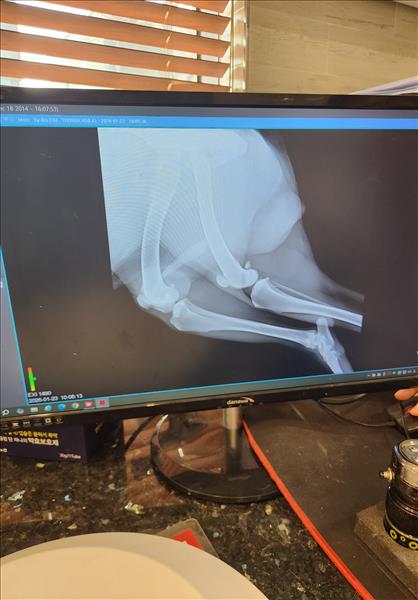

한달전에 자전거 산책이후 몇일후에 다리가 불편해 보여서 병원가서 소염진통제 처방받아서 먹이고 난뒤 몇일뒤 다리를 들기시작해서 병원가서 엑스레이도 찍었습니다. 지금 총기간이 한달정도 되었구요 미국 아키다 입니다. 체중은 40키로 정도이고요. 나이는 8.5살 정도 되는 수컷입니다. 왼쪽 다리입니다.

엑스레이 찍은 수의사님 말씀으론 뼈에는 아무 문제가 없다고 하네요.. 십자인대도 아무 문제 없다고 하시고.. 신경쪽 문제일수도 있다고 하시는대... 혹시나 다른병원을 가봐야 하는건지 너무 답답한 마음에 오늘 병원에 연락하여 엑스레이 사진 받아 왔습니다. 한번 봐주실수 있을까요. 부종같은건 없었는데 갑자기3일전부터 발바닥 조금위쪽 관절이 부종이 있는거같아요.. 만지면 불편해합니다. 갑자기 1달가까이 부종이없다가 부종이 생길수도 있나요??